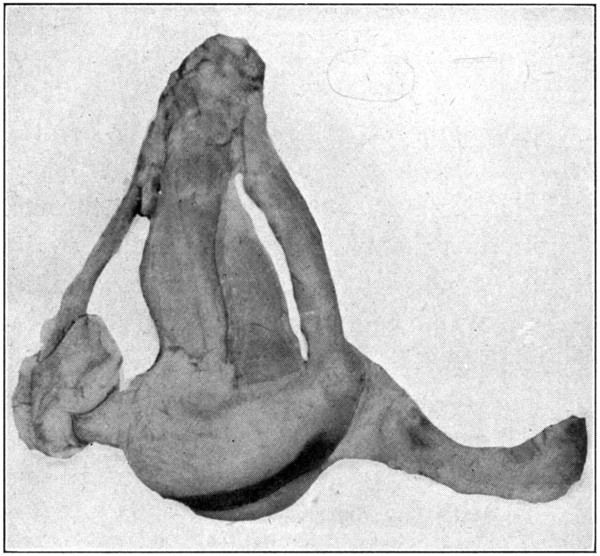

Brain, showing eyes with muscles removed, optic nerves, and chiasm.

| 0. | Brain showing eyes with muscles removed, optic nerves, and chiasm | Frontispiece |